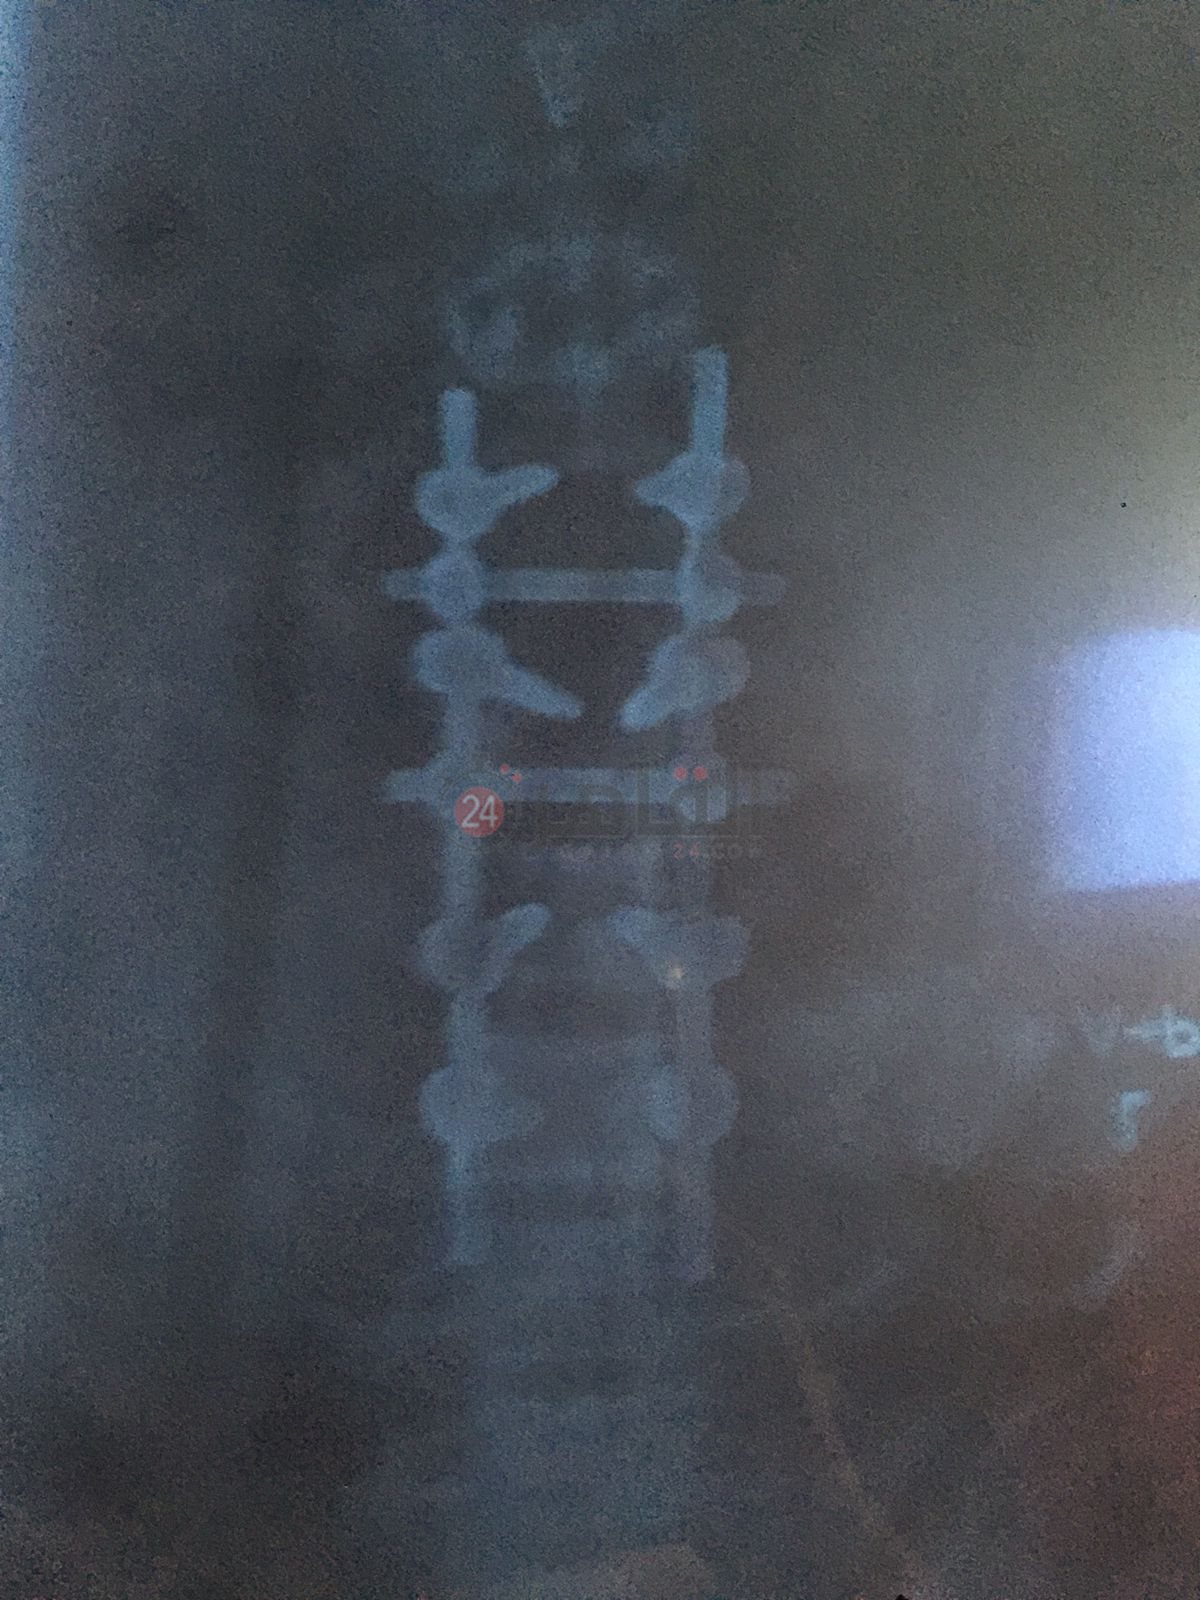

وتابع صلاح: كنتٌ أعمل بإحدى شركات الخدمات البترولية، وسقط عليّ 2 طن حديد، مما أدى إلى كسر الفقرة القطنية، مع الضغط الشديد على النخاع الشوكي، الأمر الذي أدى إلى إصابتي بضمور العضلات.